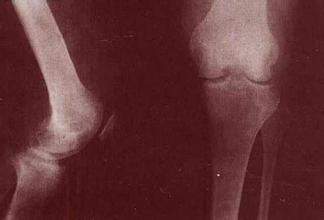

色素绒毛结节性滑膜炎没有明显的全身症状,患者体温不高,血沉不快,血象也无改变。局部症状在早期也较轻微,因此患者就诊较晚,病期较长,一般病期以1-5年者较多,半数以上有外伤史。其主要症状为关节肿胀,疼痛多比较轻微,局部皮温有时稍高,关节功能受限多不明显。呈弥漫性肿胀的关节,触及增厚的滑膜呈海绵样感觉,积液多的可触及波动感。有时可触到大小不等并稍能移动的结节。 》》》有疑问?没看明白?可点击【在线医师】咨询

膝关节受累时髌上囊及髌骨肿胀明显,积液多的浮髌试验阳性。增生的滑膜组织有时可穿破后关节囊而进入腘窝,并沿小腿后方肌间隙向下蔓延,产生深在的弥漫性肿胀。踝关节受累者肿胀在内、外踝周围较明显。髋关节受累时肿胀多位于髋关节前方。 >>>点击此处,专家一对一为您详解滑膜炎

患肢都有轻度的肌肉萎缩。关节穿刺可抽出血性或咖啡色液体,这种关节液很特殊,具有诊断价值。